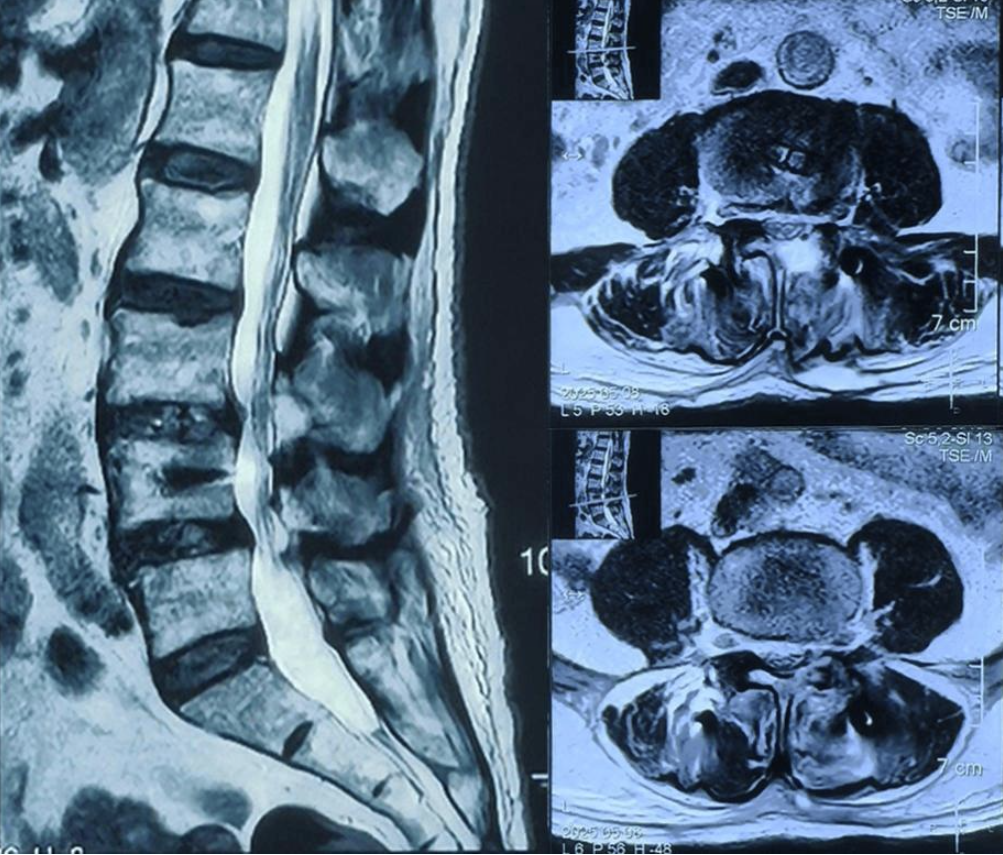

术后第1天,杨先生腰腿痛症状明显缓解;第2天,在医护人员指导下佩戴腰围即可独立行走。此次UBE镜下双间隙融合术的成功开展,让患者解除病痛折磨,重获正常生活能力。

术后核磁:神经受压解除,硬膜囊膨隆